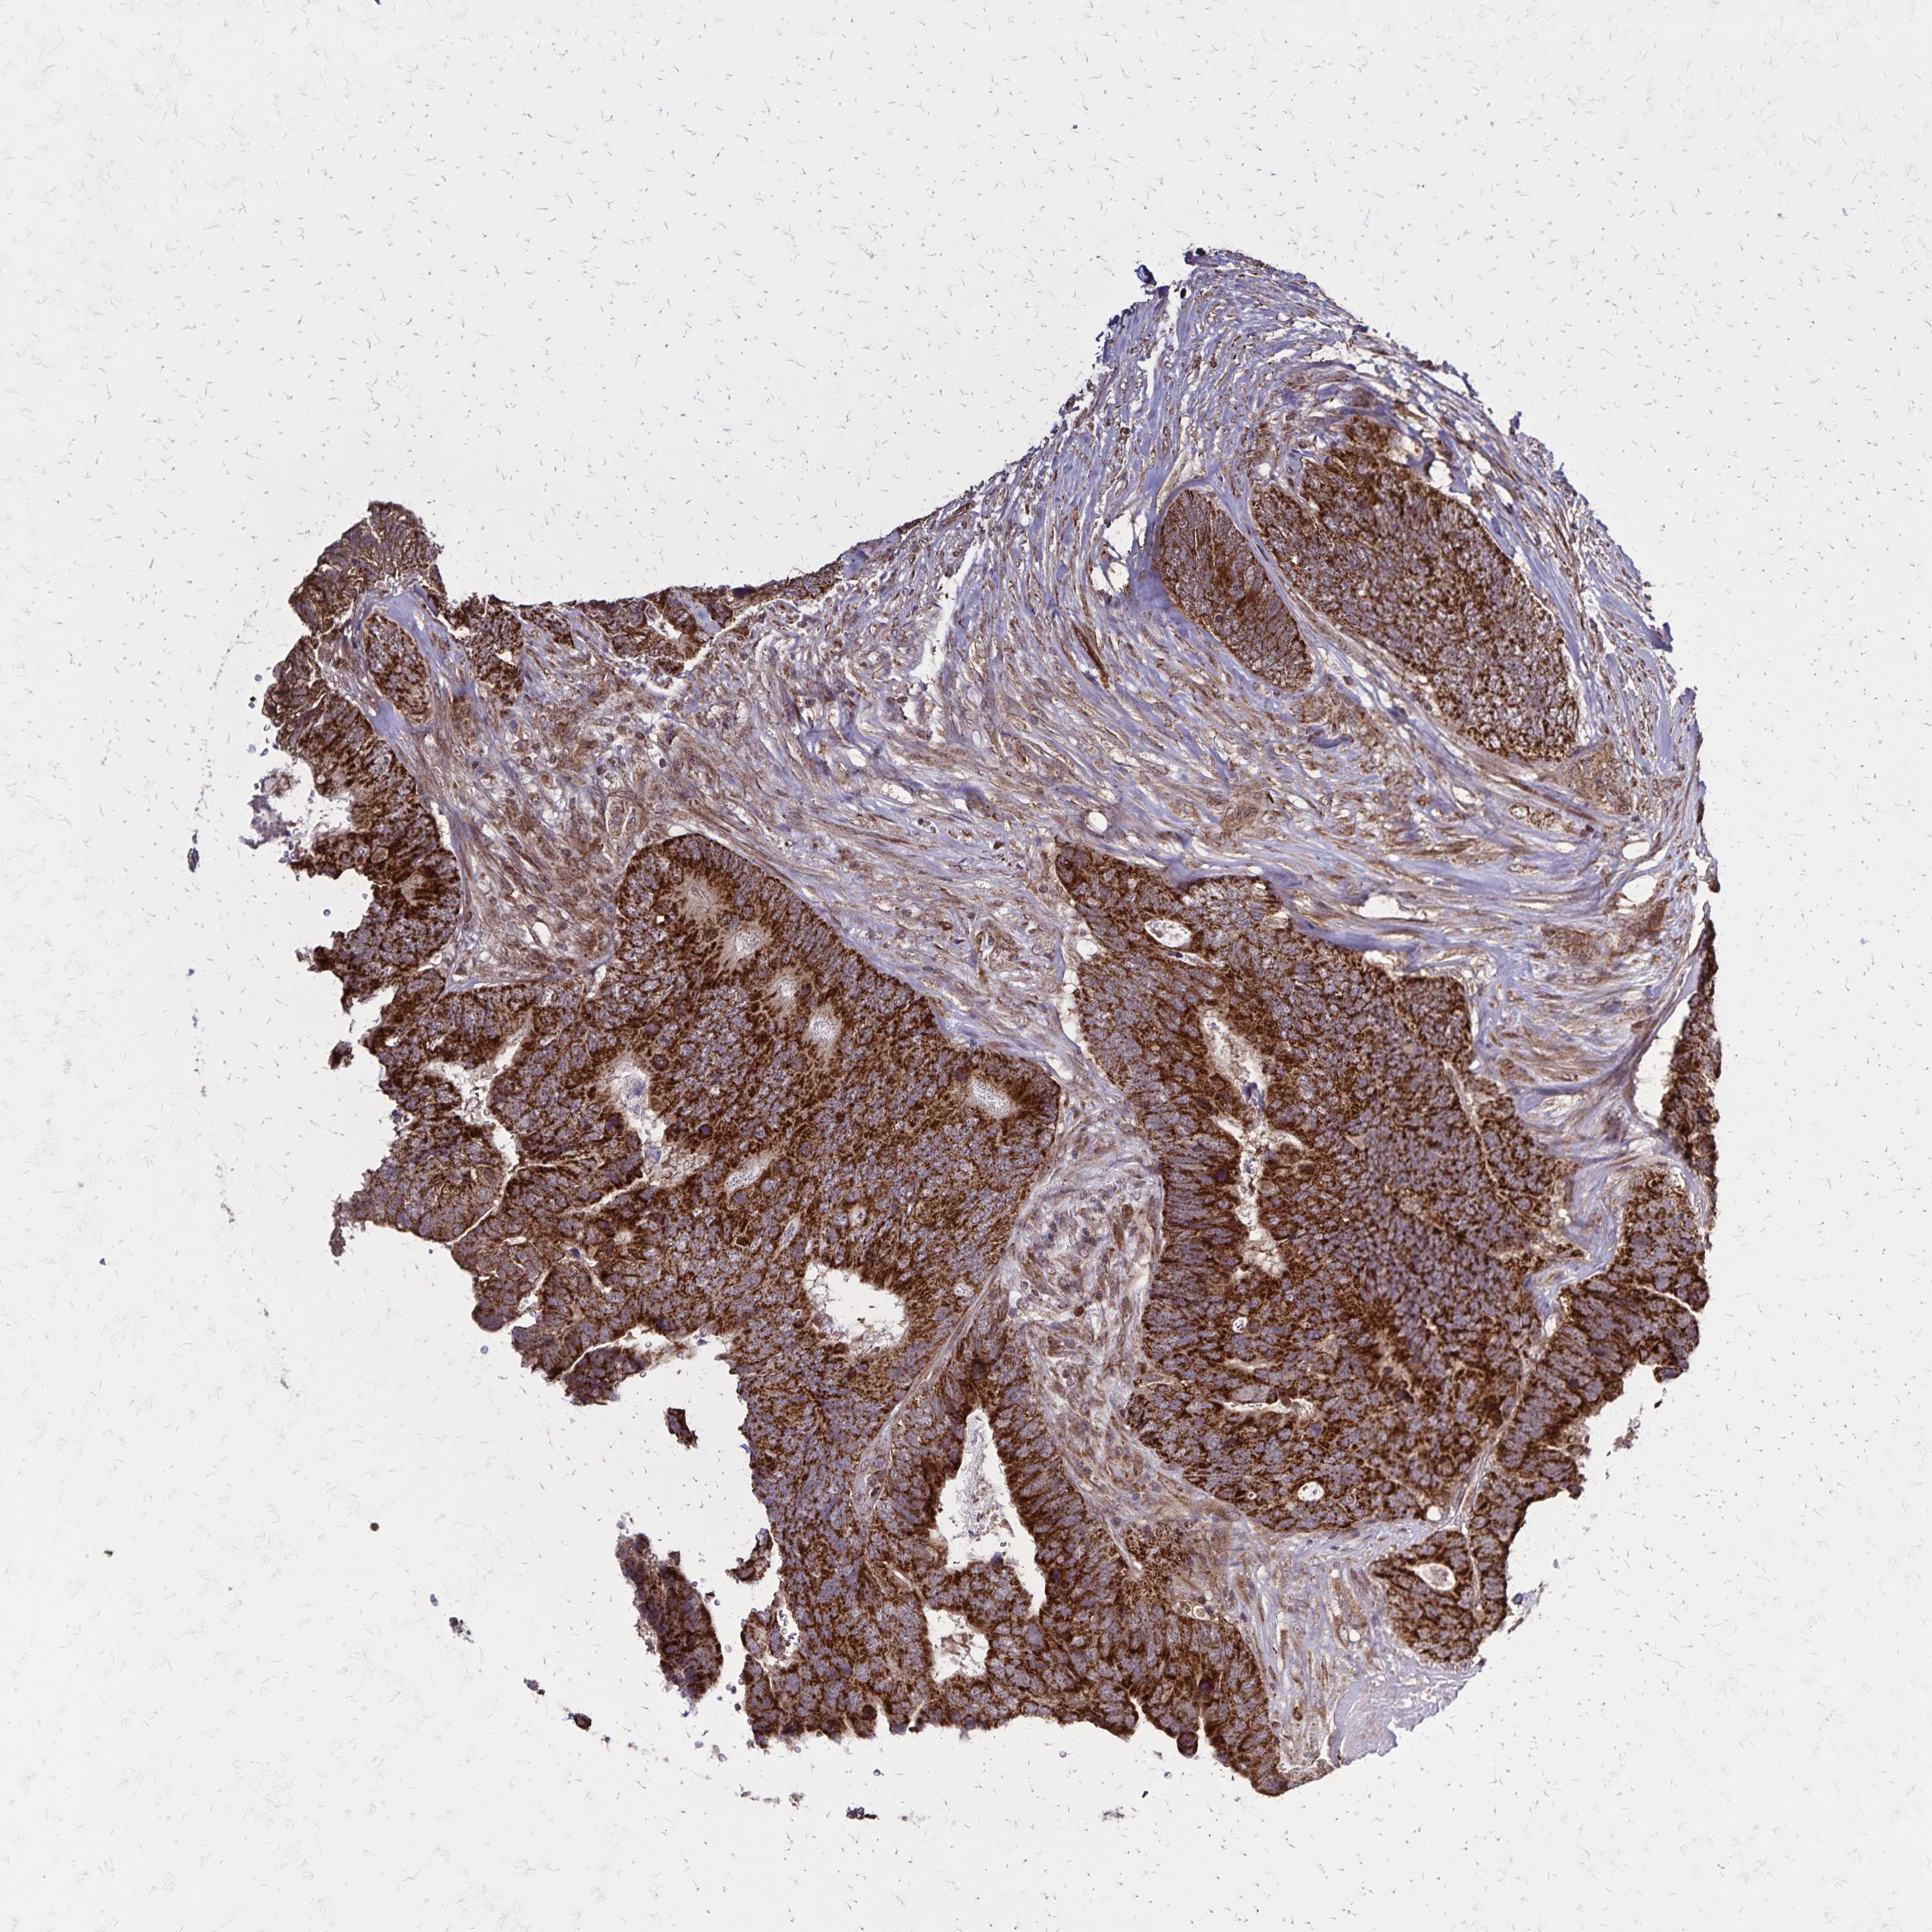

CANCER BREAST CANCER Show tissue menu

BRCA TCGA BRCA VALIDATION PROTEIN EXPRESSION

Breast cancer

Human cancer